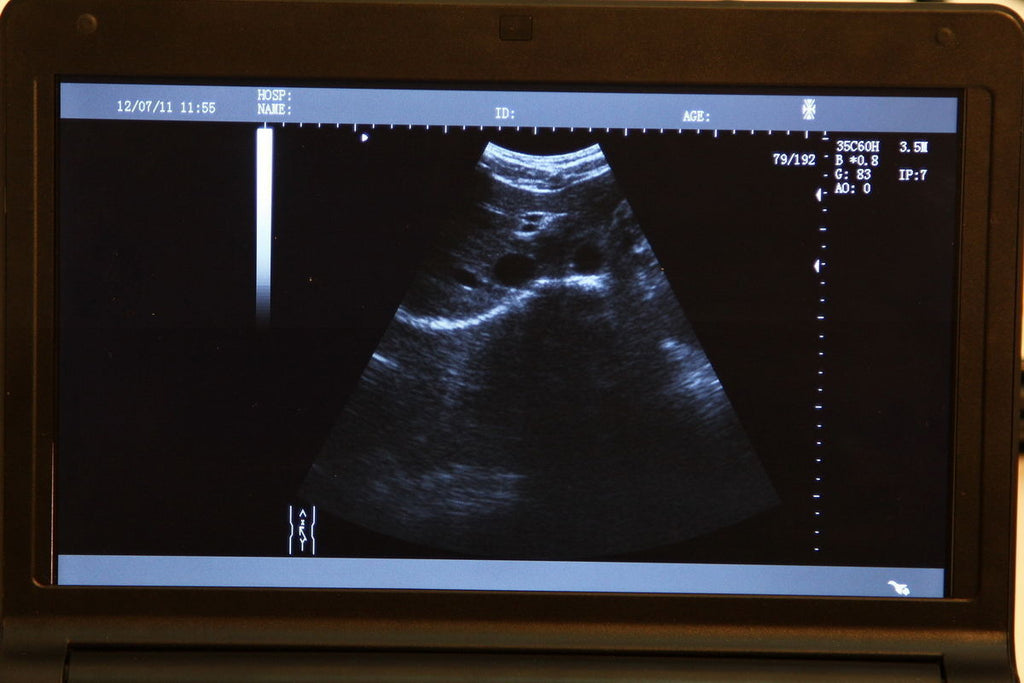

A 3D ultrasound scanner is a state-of-the-art imaging device used primarily in obstetrics. It creates detailed three-dimensional images of the fetus, providing healthcare professionals with critical information about the development and wellbeing of both the mother and baby. The 6.5 MHZ transvaginal probe enhances the accuracy of images, making it particularly useful in early pregnancy assessments. With this technology, doctors can visualize the fetus in real-time, leading to better diagnosis and treatment decisions.

Digital laptop 3D ultrasound scanners are portable and user-friendly, allowing healthcare providers to perform examinations in various settings, including clinics and hospitals. The digital format provides higher resolution images compared to traditional scanners, and since it uses advanced software, the analysis is faster and more reliable. This flexibility and efficiency revolutionize workflow, making it easier for medical professionals to access critical data quickly.